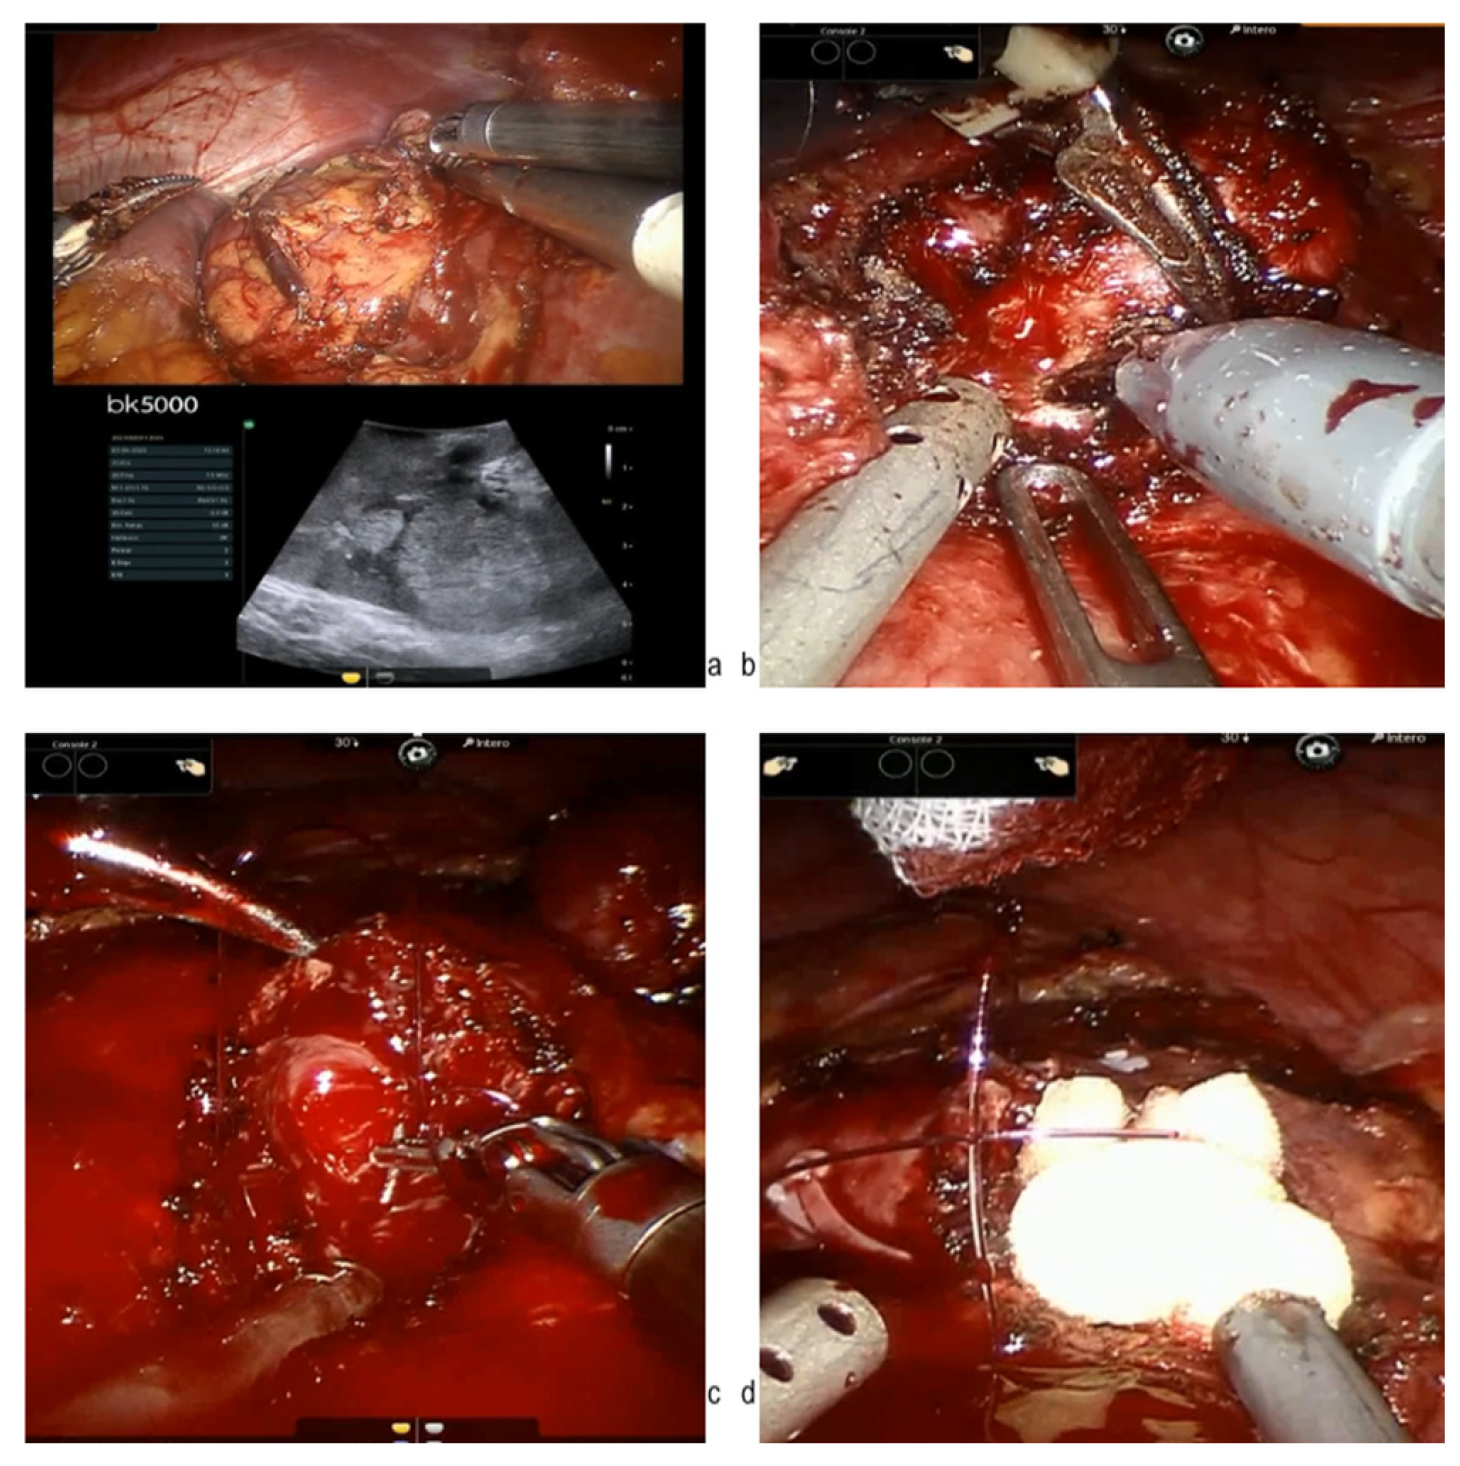

- Mihai, I.; Dura, H.; Teodoru, C.A.; Todor, S.B.; Ichim, C.; Grigore, N.; Mohor, C.I.; Mihetiu, A.; Oprinca, G.; Bacalbasa, N.; et al. Intraoperative Ultrasound: Bridging the Gap between Laparoscopy and Surgical Precision during 3D Laparoscopic Partial Nephrectomies. Diagnostics 2024, 14, 942. [Google Scholar] [CrossRef] [PubMed]

- Grosso, A.A.; Lambertini, L.; Di Maida, F.; Gallo, M.L.; Mari, A.; Minervini, A. Three-dimensional reconstruction and intraoperative ultrasonography: Crucial tools to safely approach highly complex renal masses. Int. Braz. J. Urol. 2022, 48, 966–997. [Google Scholar] [CrossRef]